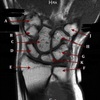

1

What is letter A?

SUPRASPINATUS TENDON

2

What is letter B?

ACROMION

3

CORACOID PROCESS

4

5

What is letter C?

6

What is letter D?

7

8